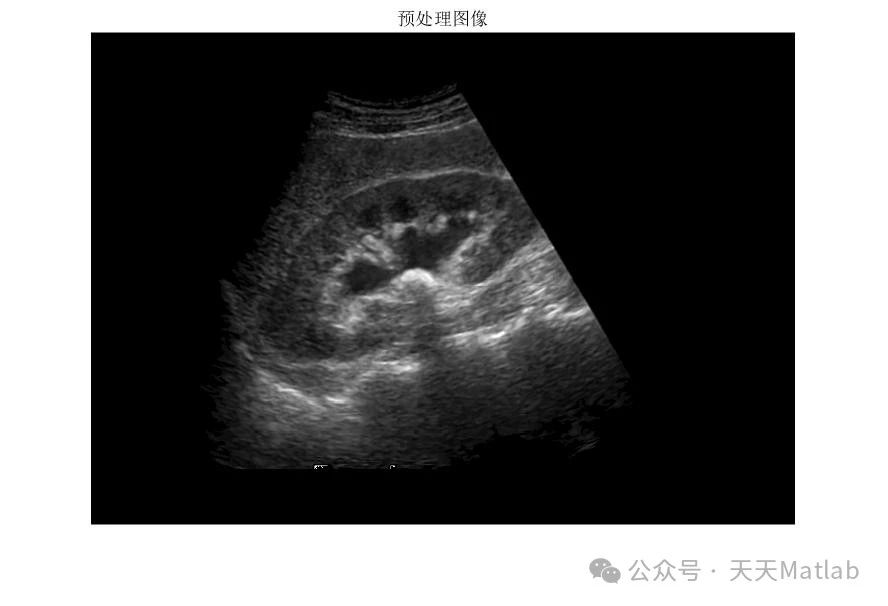

一、 医学图像预处理:中值滤波的应用

医学影像数据通常包含各种噪声,例如椒盐噪声、高斯噪声等,这些噪声会严重影响图像的质量,从而干扰后续的结石识别和长度测量。中值滤波是一种非线性滤波方法,其基本原理是将图像中每个像素点的灰度值替换为其邻域像素灰度值的中值。与均值滤波相比,中值滤波对椒盐噪声具有更强的抑制能力,能够有效去除孤立的噪声点,同时更好地保留图像的边缘细节。在肾结石检测中,由于结石边缘往往比较锐利,因此中值滤波可以有效去除噪声,同时避免过度平滑导致结石边缘模糊不清,从而提高后续图像分割和测量精度。

具体而言,中值滤波的实现步骤如下:

确定滤波窗口大小: 滤波窗口大小的选择会影响滤波效果。较小的窗口能够更好地保留细节,但噪声去除效果较弱;较大的窗口能够有效去除噪声,但可能会导致细节损失。因此,需要根据图像的噪声水平和结石大小选择合适的窗口大小,通常为3×3或5×5。

计算窗口内像素灰度值的中值: 将滤波窗口在图像上滑动,每次计算窗口内所有像素的灰度值,并将其排序,取中间值作为该窗口中心像素的新灰度值。

替换像素灰度值: 将计算得到的中值替换原图像中对应像素点的灰度值。

重复步骤2和3: 直到处理完图像中的所有像素点。

⛳️ 运行结果